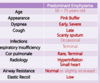

- Describe COPD that is predominantly emphysema as it relates to everything listed

- Both emphysema and bronchitis present with SOB. What are the other 2 main presentations for bronchitis?

Understand and be able to discuss common bacterial pathogens responsible for upper respiratory tract infections, including those that present as sinusitis, pharyngitis, epiglottitis.